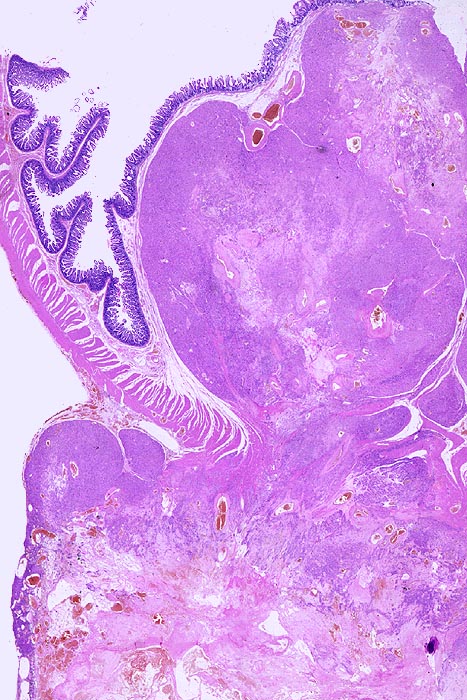

• Scharf begrenzter kugeliger Tumor in der Submukosa des Magenantrums

• Über dem Tumor entzündungsfreie Antrumschleimhaut mit partiell reepithelialisiertem oberflächlichem Ulkus (Quellungsfibrinoid).

• Herdförmig pseudozystische Auflockerung des Tumorgewebes.

• Risikostratifikation nach Miettinen und Lasota (2006): Very low risk (sehr niedriges Risiko für Metastasen oder tumorbedingte Mortalität): Lokalisation im Magen, Grösse 22mm, fehlende Mitosen.